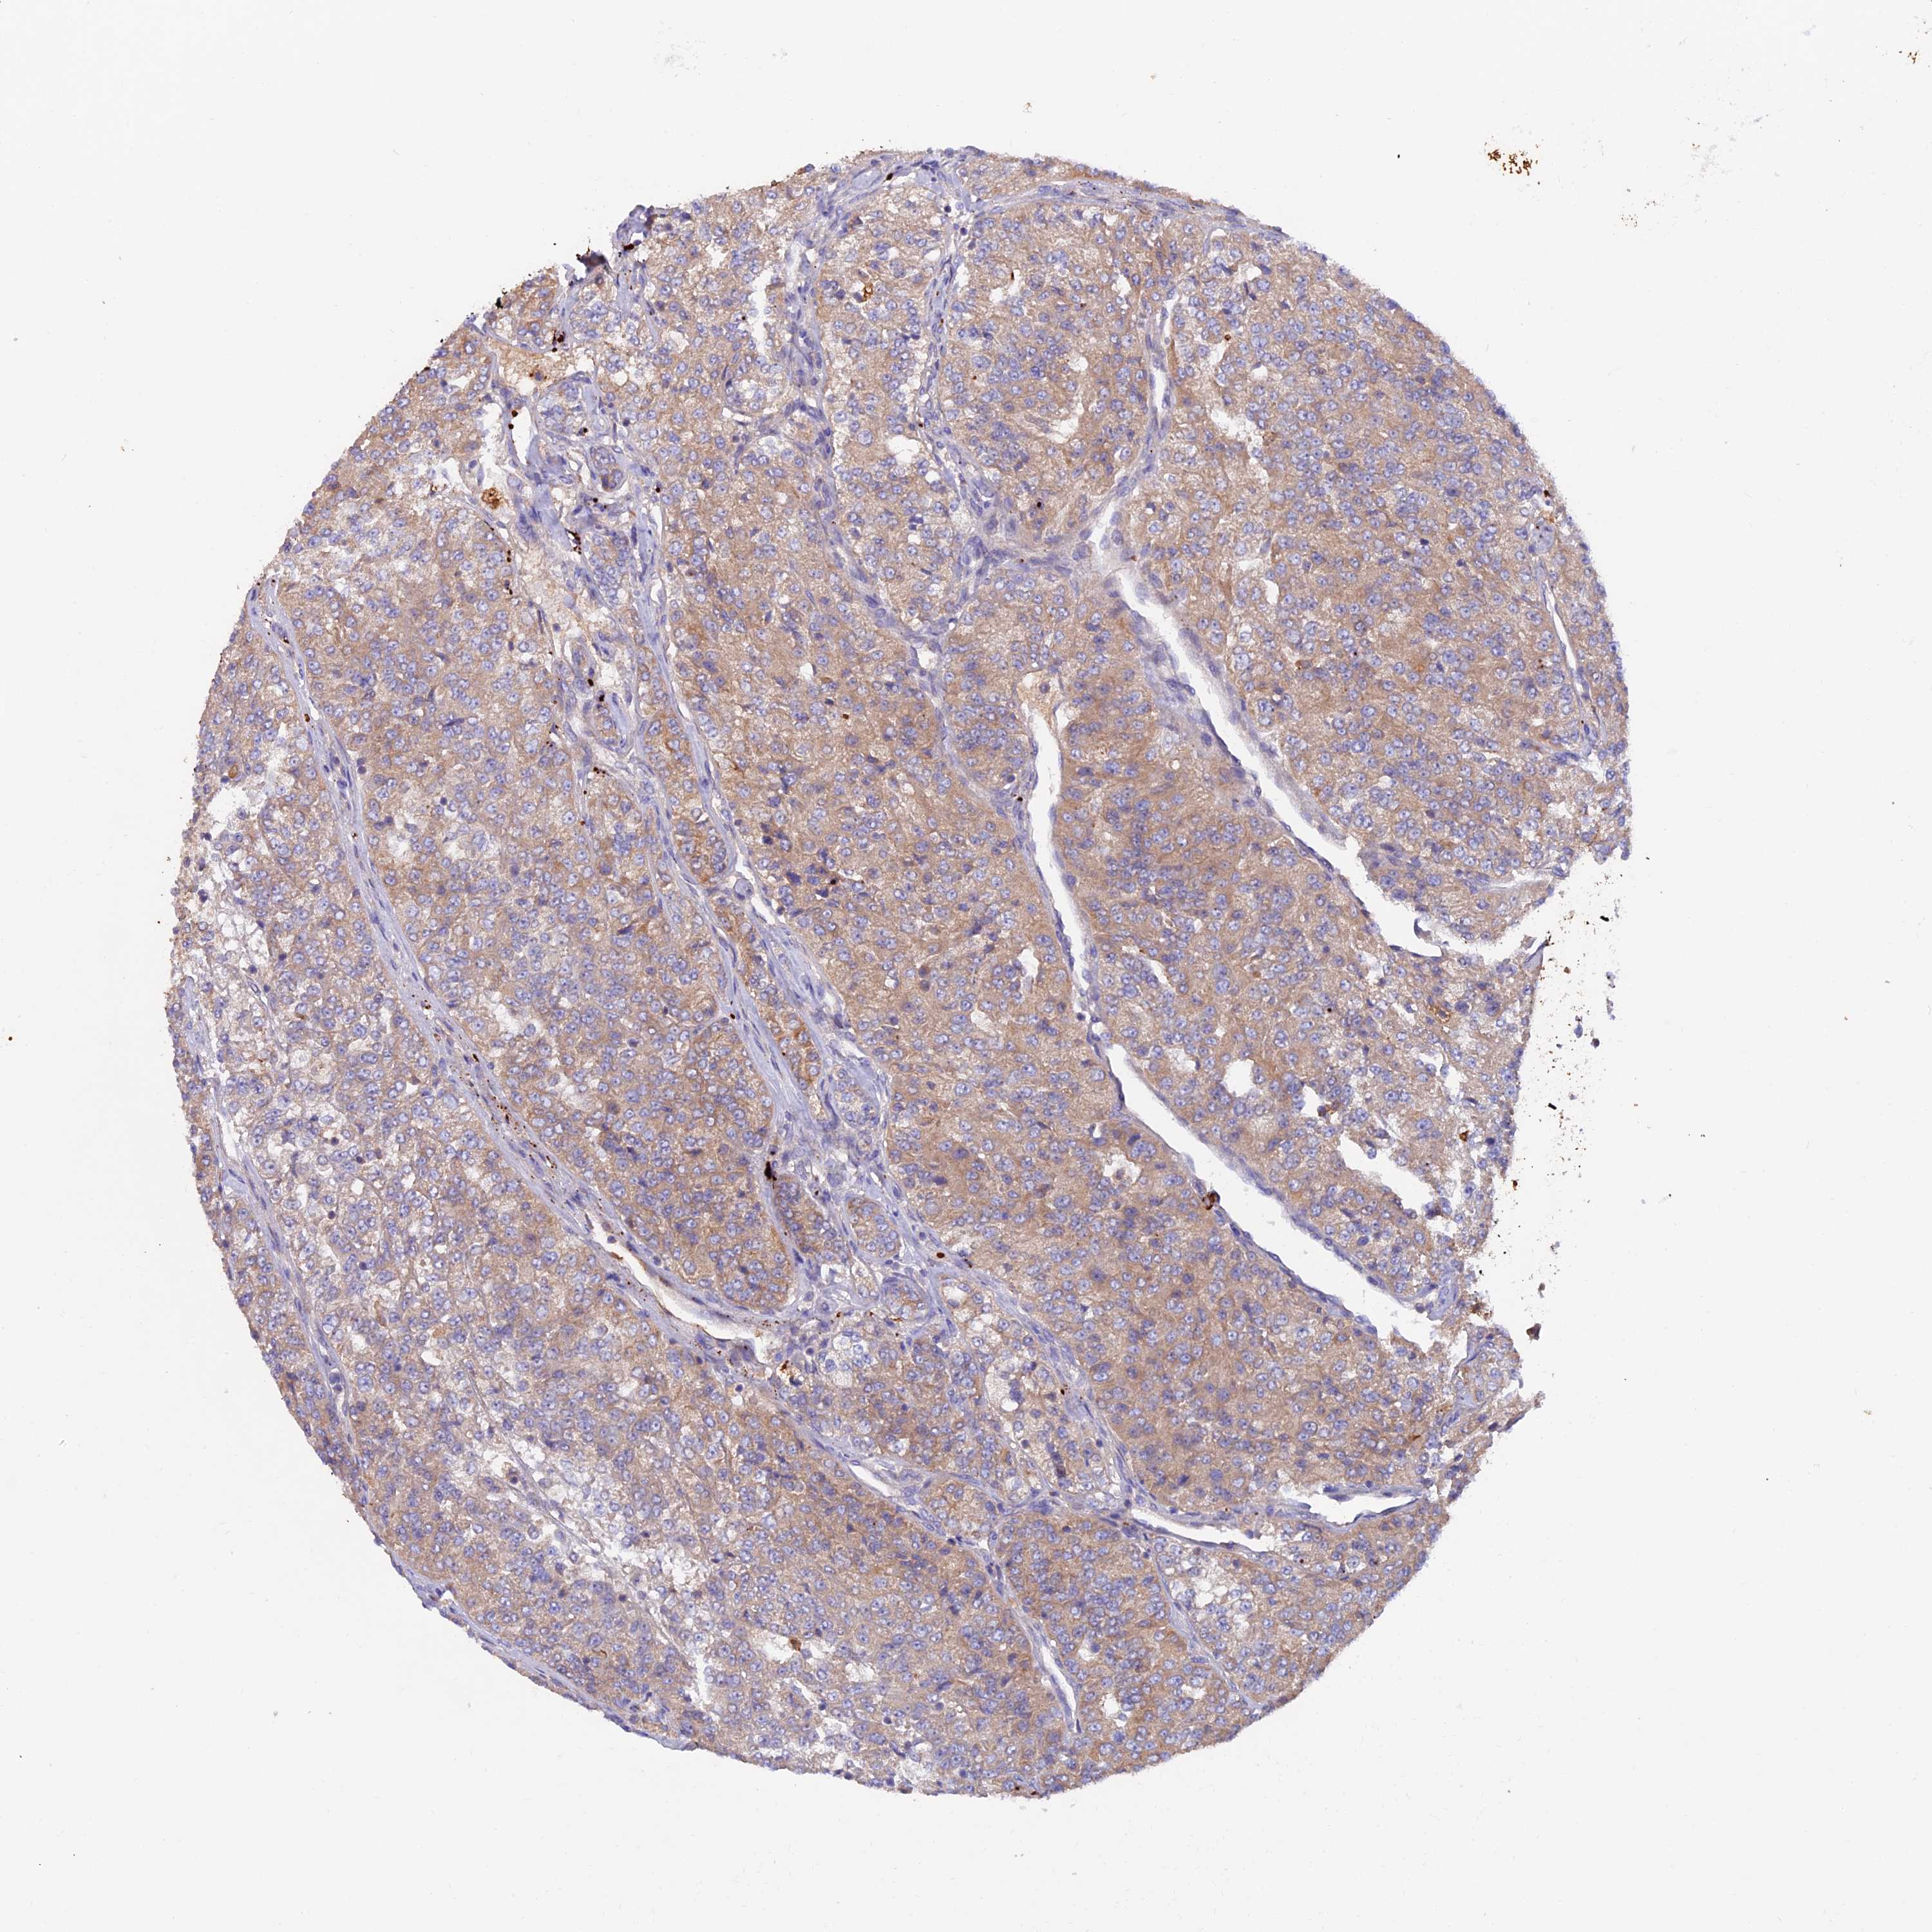

KIDNEY RENAL CLEAR CELL CARCINOMA (VALIDATION) - Interactive survival scatter ploti

The Survival Scatter plot shows the clinical status (i.e. dead or alive) for all individuals in the patient cohort, based on the same data that underlies the corresponding Kaplan-Meier plots. Patients that are alive at last time for follow-up are shown in blue and patients who have died during the study are shown in red.

The x-axis shows the expression levels (FPKM) of the investigated gene in the tumor tissue at the time of diagnosis. The y-axis shows the follow-up time after diagnosis (years). Both axes are complimented with kernel density curves demonstrating the data density over the axes. The top density plot shows the expression levels (FPKM) distribution among dead (red) and alive patients (blue). The right density plot shows the data density of the survived years of dead patients with high and low expression levels respectively, stratified using the cutoff indicated by the vertical dashed line through the Survival Scatter plot. This cutoff is automatically defined based on the FPKM cutoff that minimizes the p-score. The cutoff can be changed by dragging the vertical line or by entering a cutoff value in the square labeled "Current cut-off".

Under the Survival Scatter plot the p-score landscape (black curve; left axis) is shown together with dead median separation (red curve; right axis). Dead median separation is the difference in median mRNA expression between patients who have died with high and low expression, respectively. It is calculated as follows: median FPKM expression of dead patients with high expression - median FPKM expression of dead patients with low expression. This is intended to aid the user in visually exploring custom cutoffs and the associated p-scores and dead median separation.

Individual patient data is displayed and can be filtered by clicking on one or more of the category buttons on the top of the page. Categories describing expression level and patient information include: high, low, alive, dead, female, male and tumor stages. The scale of the x-axis can be toggled between linear and log-scale by clicking on the "x log" button. Mouse-over function shows TCGA ID, patient information and mRNA expression (FPKM) for each patient.

& Survival analysisi

Kaplan-Meier plots summarize results from analysis of correlation between mRNA expression level and patient survival. Patients were divided based on level of expression into one of the two groups "low" (under cut off) or "high" (over cut off). X-axis shows time for survival (years) and y-axis shows the probability of survival, where 1.0 corresponds to 100 percent.

PTPN9 is validated prognostic, high expression is favorable in Kidney Renal Clear Cell Carcinoma (validation)

Best expression cut offi

Based on the FPKM value of each gene, patients were classified into two groups and association between prognosis (survival) and gene expression (FPKM) was examined. The best expression cut-off refers the FPKM value that yields maximal difference with regard to survival between the two groups at the lowest log-rank P-value. Best expression cut-off was selected based on survival analysis .

When clicking on this number, the vertical dashed line indicating cut-off, the interactive survival plot, and the Kaplan-Meier curve will be adjusted to show results based on the best expression cut-off.

: 19.16

TCGA RNA samplesi

RNA-seq data is reported as average FPKM (number Fragments Per Kilobase of exon per Million reads), generated by the The Cancer Genome Atlas (TCGA) .

Normal distribution across the dataset is visualized with box plots, shown as median and 25th and 75th percentiles. Points are displayed as outliers if they are above or below 1.5 times the interquartile range. FPKM values of the individual samples are presented next to the box plot.

Average pTPM 25.3

Number of samples 100